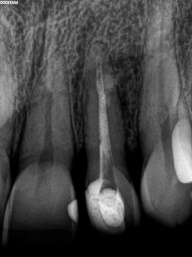

Perfurações dentarias são complicações no tratamento de canal que na maioria dos casos resulta em um prognóstico desfavorável, pois permite a entrada de microrganismos nos tecidos que envolvem o dente. Em alguns casos, devido ao seu difícil diagnóstico, acesso limitado, tempo decorrido ou tamanho da perfuração resultará em um desafio para o profissional conseguir um selamento adequado da área, sendo muito importante o conhecimento sobre o material que será empregado.